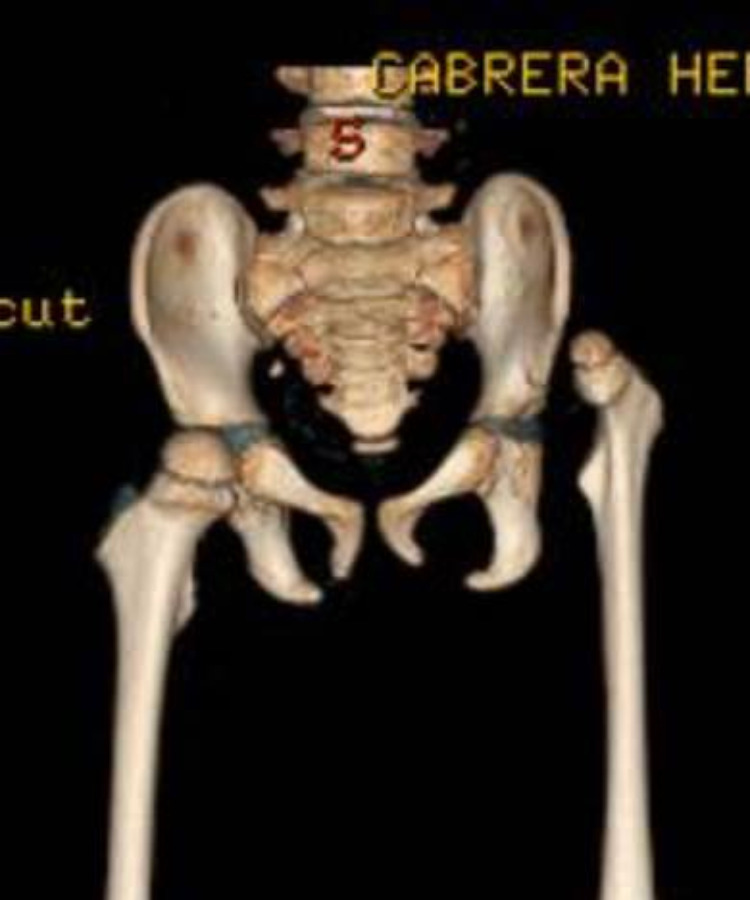

Técnicas quirúrgicas pediátricas restauran función y apariencia de extremidades con lesiones graves o deformidades congénitas, buscando mejorar funcionalidad y estética.

Las deformidades de pie y rodilla incluyen genu varo, genu valgo, pie plano y pie cavo, con causas congénitas o postraumáticas.